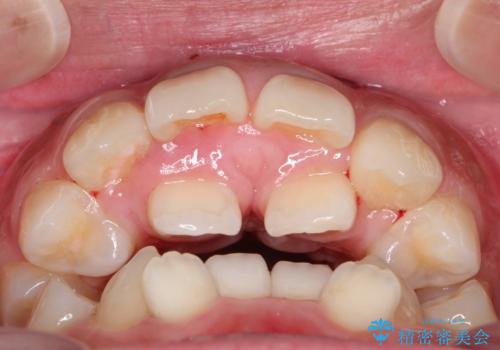

人生が変わる 困難を極める咬合状態に歯列矯正単独で挑戦する

- 上顎の骨格性拡大+両側第1小臼歯抜歯 によりスペースを獲得、フルリンガルによるワイヤー矯正を計画した。

骨格的要因を背景にもつ不正咬合のため、歯列矯正単独での改善は困難と判断しましたが、患者さんとの相談の結果、歯列矯正単独で可能なところまで一緒に頑張りましょうということで、治療をすすめました。

シビアな叢生や開咬も改善することができ、想像以上の改善に時間をかけた甲斐があったと満足していただけました。